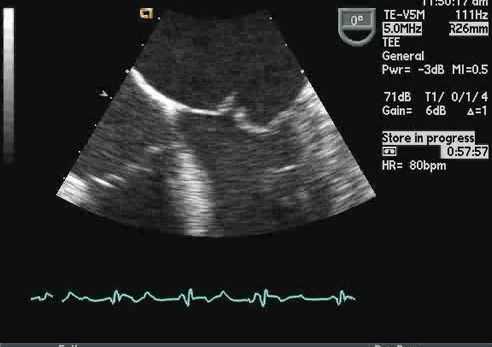

При выявлении препятствий для прохождения ультразвука (ожирение, присутствие искусственных клапанов) и при тяжелых заболеваниях сердца используют чрезпищеводную ЭхоКГ, во время которой датчик вводят через пищевод вплотную к левому предсердию. В течение 4—6 часов до процедуры пациент должен воздержаться от курения, не употреблять воду и пищу. Также следует извлечь съемные зубные протезы, если таковые имеются.

ЭхоКГ не позволяет отличить доброкачественные опухоли от злокачественных. 2-D эхокардиография показывает опухоли как эхогенные образования в полости сердца, прикрепленные к стенке или находящиеся в перикарде. Обычно их размер и мобильность можно хорошо определить. Как и во всех исследованиях при проведении ЭхоКГ, необходимо получить несколько изображений. Иногда в M-режиме можно увидеть опухоль, такую как миксома, нарушающая функцию клапана. Эффекты опухолей (например, обструкция клапана, дисфункция ЛЖ из-за инфильтрации, обструкции или перикардиального выпота) также можно увидеть на эхокардиографии.

Двухмерная визуализация - лучший метод ЭхоКГ для выявления тромба, который обычно является ярким. Однако это не всегда так, и бывает очень сложно отличить тромб от миокарда, если они имеют аналогичную эхогенность. Чреспищеводная эхокардиография может быть полезной, особенно при тромбах ушка левого предсердия.

Всегда следует делать несколько томографических срезов на ЭхоКГ. На 2-D эхокардиографии тромб может быть виден как шарообразное образование или образование в виде лозы, или как хорошо организованное ламинированное возвышенное утолщение в ЛП или ЛЖ. В ЛП могут быть ассоциированные признаки вялого кровотока, такие как «спонтанное контрастирование». Ушко левого предсердия может содержать тромб, который можно идентифицировать на чреспищеводной эхокардиографии.